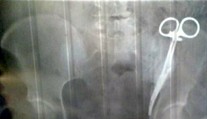

Viac ako 20 rokov má v tele chirurgické nožnice, zašili jej ich počas cisárskeho rezu Róbert Ďurkáč 19. 6. 2019